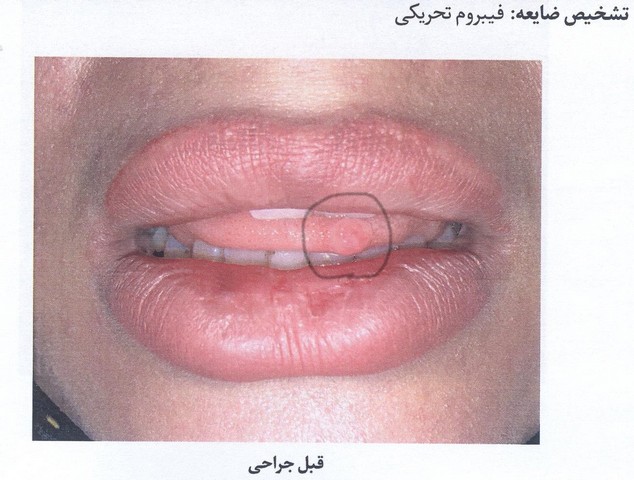

فیبروم تحریکی چیست؟ فیبروم تحریکی شایع ترین ضایعه واکنشی بافت دهان می باشد، هر چند این که فیبروم یک نئوپلاسم حقیقی است یا هایپرپلازی واکنشی ( افزایش تعداد سلولی نسبت به یک محرک موضعی ) بافت همبندی فیبروزه در پاسخ به تحریک موضعی ( اصطکاک ) یا تروما ( ضربه موضعی ) می باشد که اغلب در راستای خط جویدن گونه (پلان اکلوزال) به دلیل گاز گرفتگی گونه یا زبان بوجود می آید... -